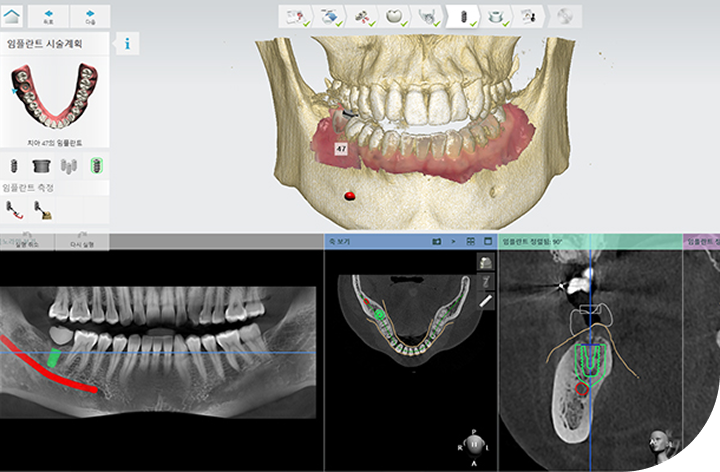

환자의 구강 정보를 디지털 데이터를 기반으로

3D 가상 모의 수술을 진행해 기존 방식 대비 수술 시간이 짧아

체력적 부담을 줄여주고 최소 절개로 통증 및 붓기 최소화로

면역력이 약하거나 회복력이 더딘 고령의 환자, 고혈압 당뇨 등

전신질환을 앓고 계신 분들도 부담없이

안전하게 수술받을 수 있습니다.

디지털 정밀 진단 기반

치료 설계

3D CT, 구강스캐너 등 정밀 진단 데이터를 기반으로

잇몸뼈 상태, 신경 위치, 교합 등, 환자 개개인의

해부학적 구조를 0.1mm 단위까지 파악하여,

안전하고 이상적인 치료 계획을 수립합니다.